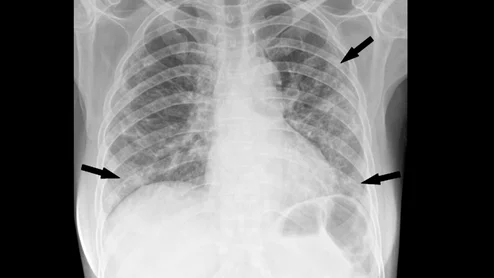

Chest radiograph in a 53-year-old woman with confirmed coronavirus disease 2019, or COVID-19, pneumonia. The patient had fever and cough for 5 days. Multifocal patchy opacities (arrows) can be seen in both lungs. Image courtesy of RSNA. What COVID looks like ob CT medical imaging.